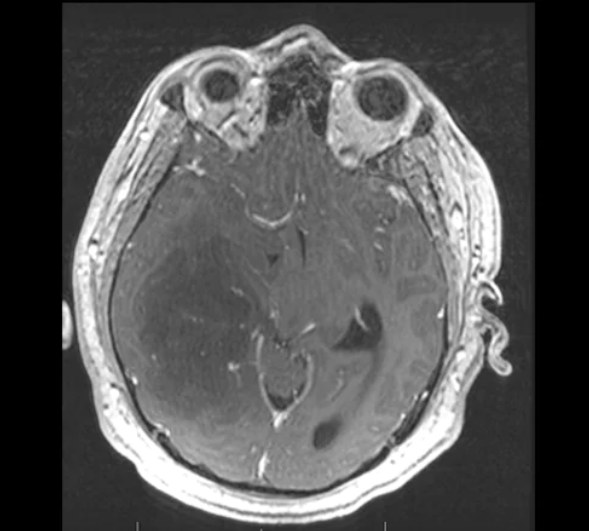

一名55歲男性表現為進行性意識模糊和左側偏癱。MRI顯示囊性腫塊,周圍呈環狀強化,並透過胼胝體輕微延伸(單箭頭)。FLAIR序列顯示中線移位的廣泛血管源性水腫(虛線箭頭)。行開顱手術以切除膠質母細胞瘤(WHO IV級膠質瘤)。

膠質母細胞瘤是成人最常見的原發性腦腫瘤,患者的中位生存時間較差,為15個月,5年生存率低於2%。然而,一些因素可能有助於更好的結果,如異檸檬酸脫氫酶1(IDH-1)突變狀態、06-甲基鳥嘌呤-DNA-甲基轉移酶(MGMT)甲基化和腫瘤位置。